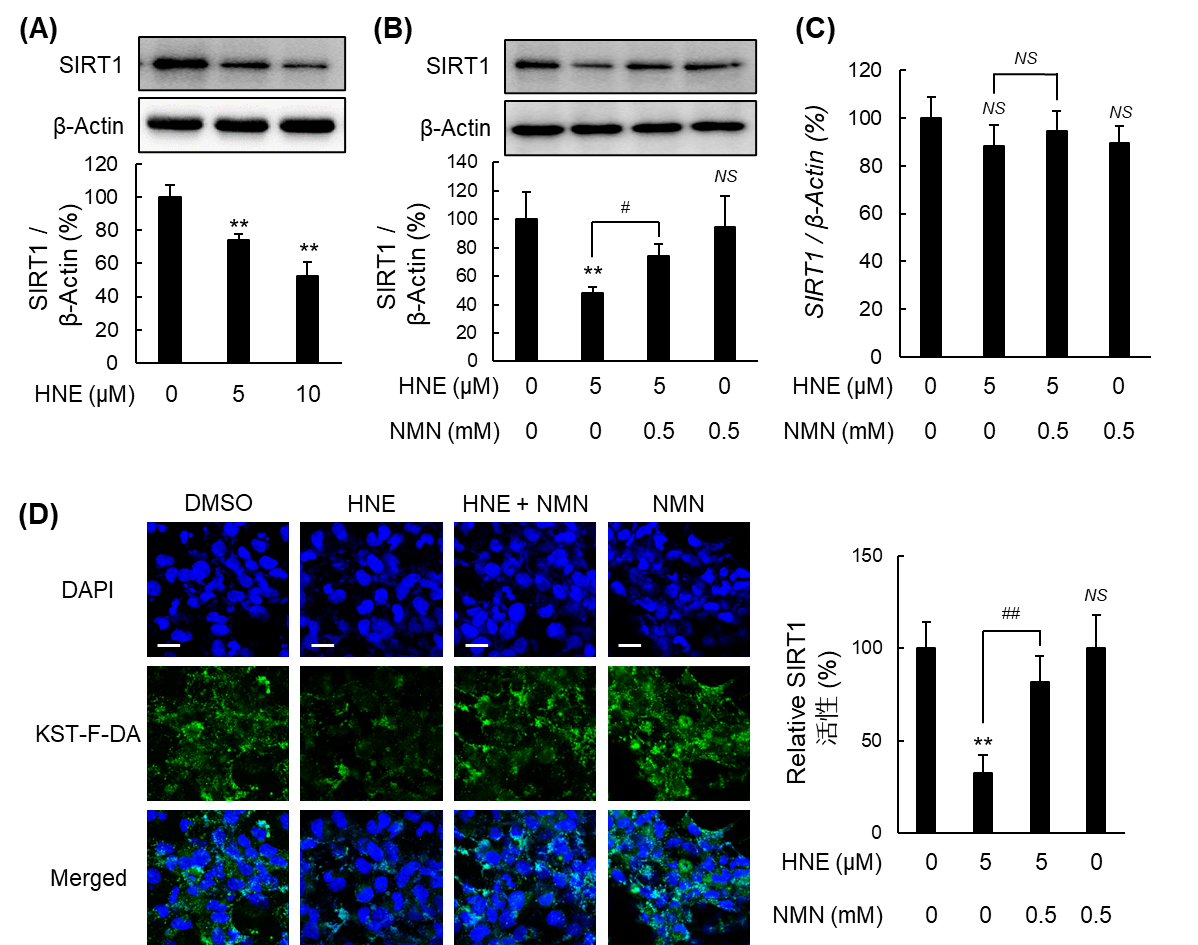

次に、NAD+前駆体であるNMNの保護効果を検証しました。NMNの事前投与によって、HNEによる細胞老化を有意に抑制し、低下した細胞内NAD+レベルと長寿遺伝子SIRT1のタンパク質発現および酵素活性を回復させました。特筆すべきは、NMNがミトコンドリアの膜電位を維持し、ROS産生を抑えることで細胞を保護した点です。さらに、HNEはSIRT1の不活性化を介して脂肪酸代謝酵素の発現を低下させ、細胞内に過剰な脂質蓄積を招きますが、NMNはこの代謝経路を正常化することで脂質蓄積を劇的に改善しました。以上の結果から、NMNはSIRT1を介した多角的なメカニズムにより、肝星細胞の抗老化と機能維持に寄与することが示唆されました。

図2. HNE誘導性SIRT1活性低下に対するNMNの抑制効果

(A, B) SIRT1タンパク質発現. (C) SIRT1 mRNA発現. (D) SIRT1活性. *KST-F-DA:SIRT1活性評価プローブ